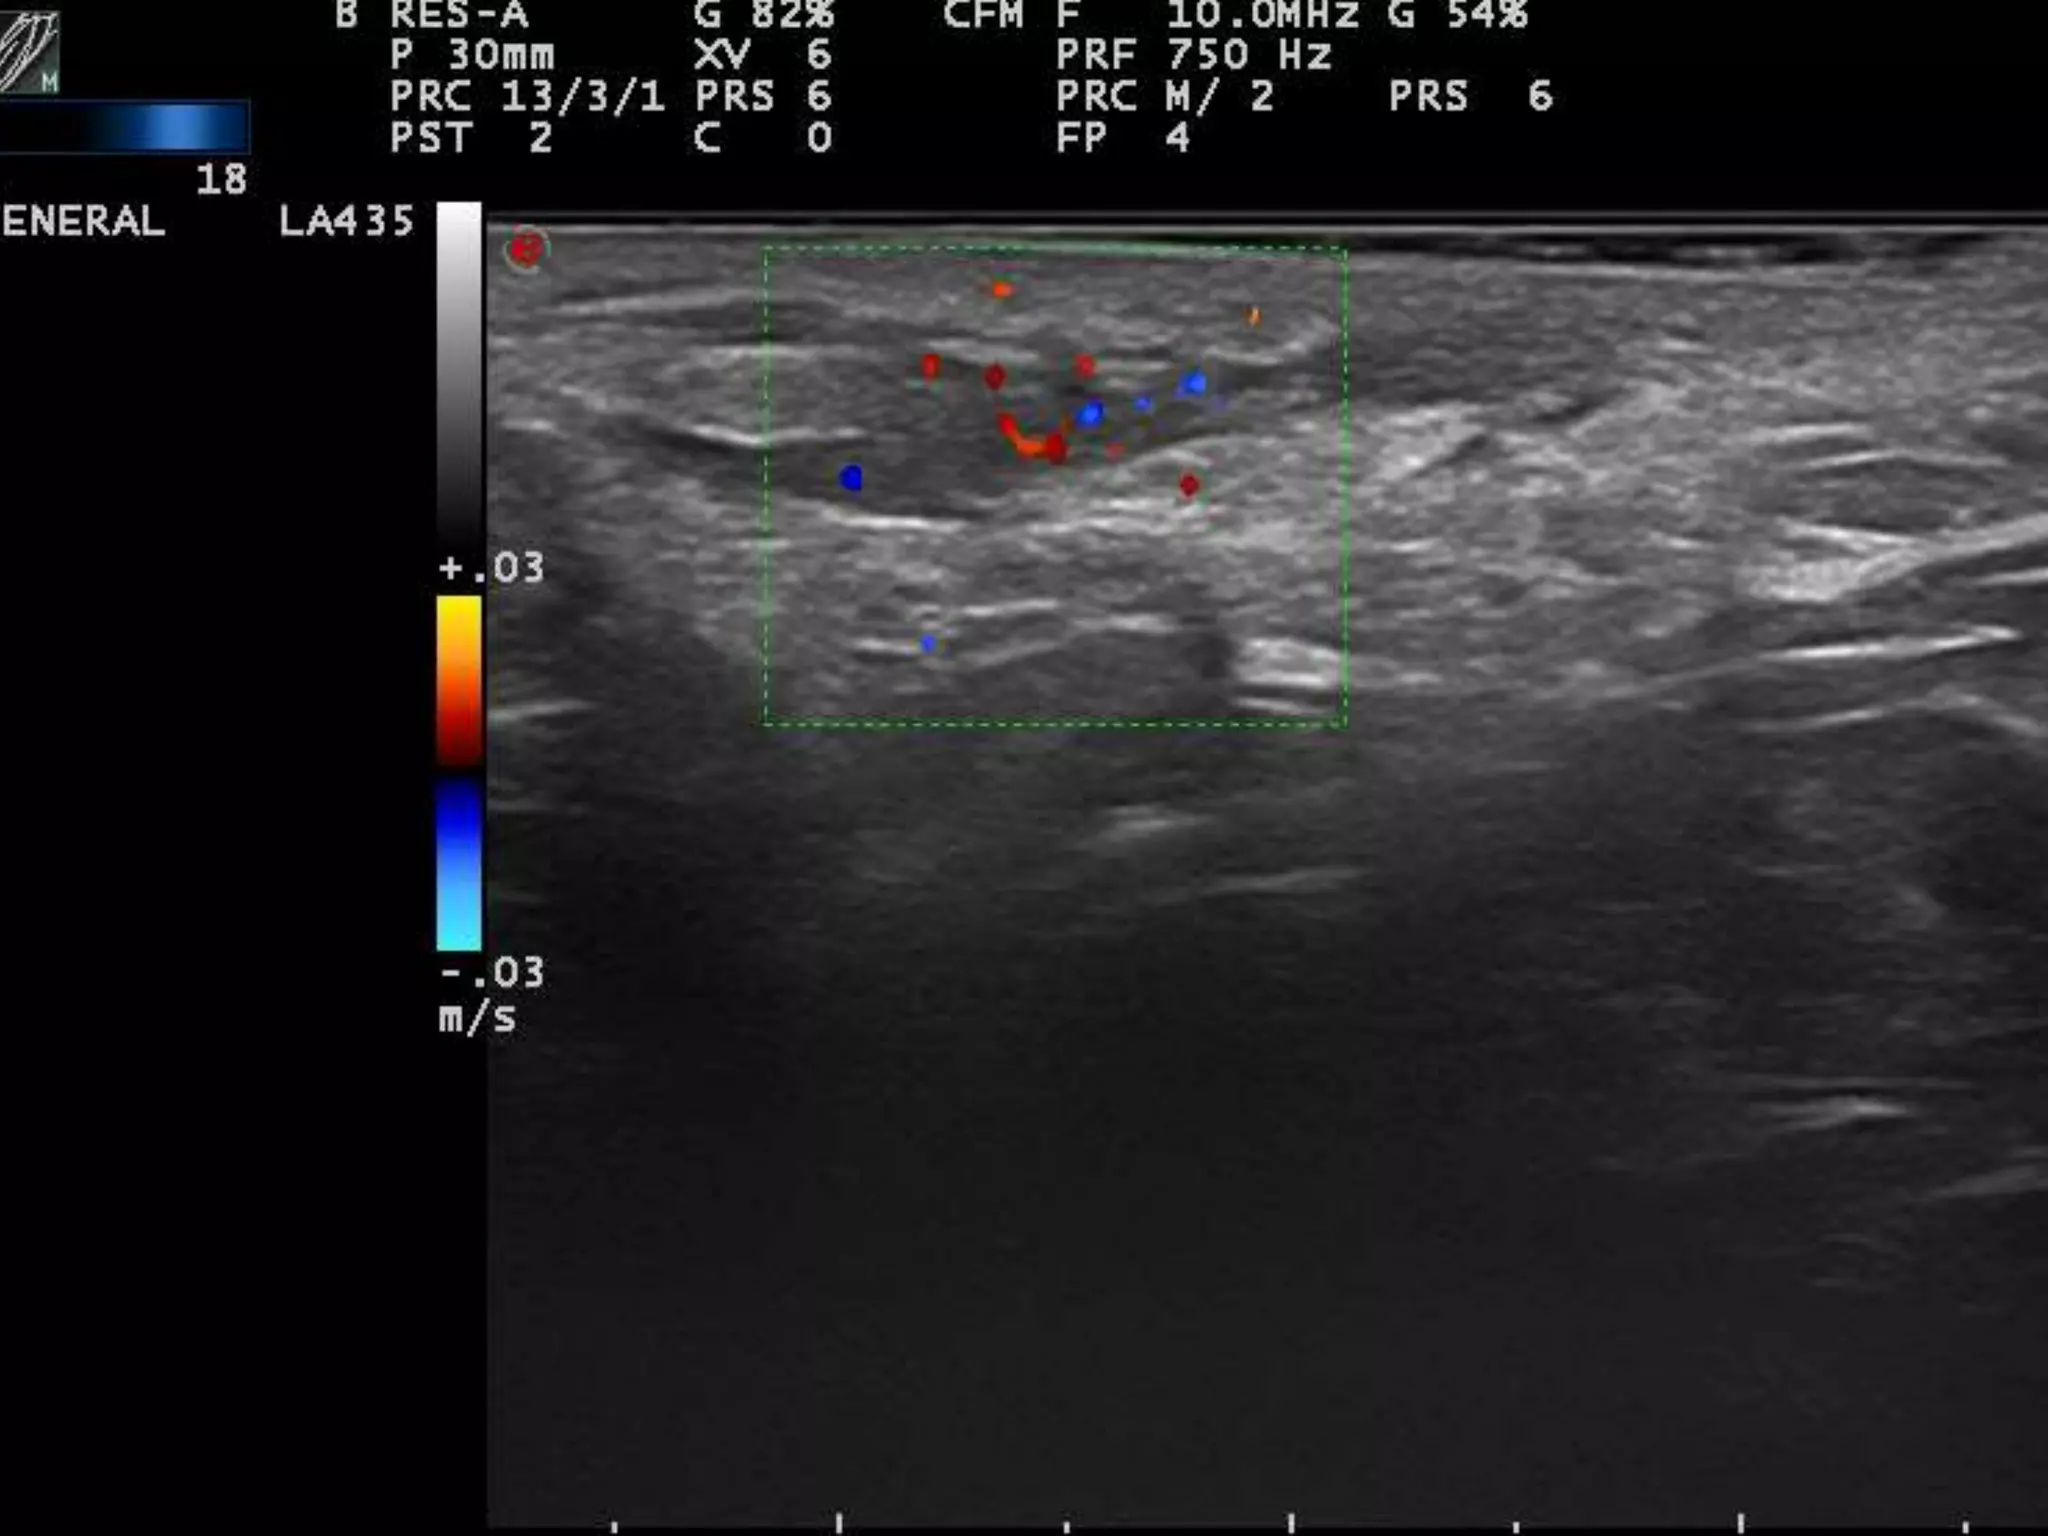

REGLAS “FÁCILES”

PARA DETECTAR INFLAMACION

1)La estructura inflamada se suele hacer

Hipoecoica = edema+células

2)El flujo Doppler Suele estar aumentado=

Aumento de flujo sanguíneo

3) COMPARAR, COMPARAR, COMPARAR

INFLAMADO

LOCALIZACION DE INFLAMACION

DERMIS

ACNE PAPULOPUSTULOSO